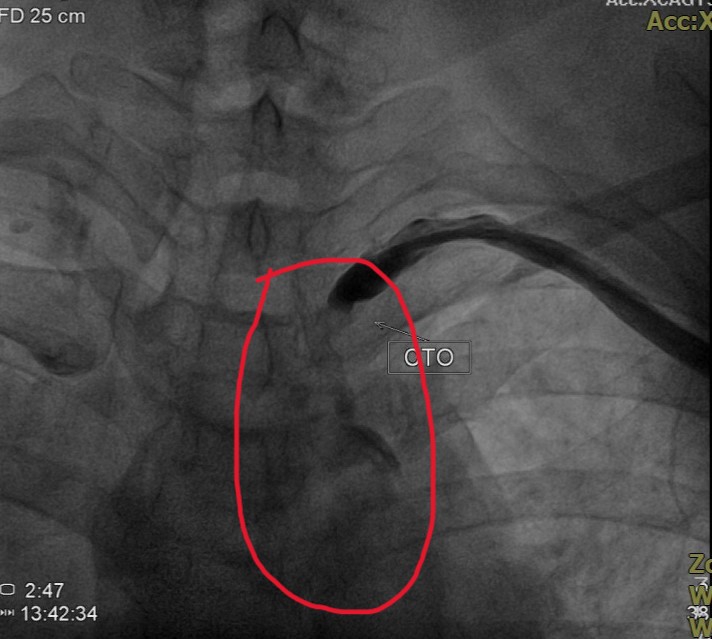

這名中年女病患的頭暈症狀,持續多年,她是洗腎患者,半年多前因洗腎血流量不足,向員榮醫院心臟外科主任賴金湖求助,賴主任為患者打通洗腎廔管,但動脈壓力仍低,頭暈仍在,賴主任推測罹患「鎖骨下動脈竊血症候群」,經血管攝影確定後,為患者施行導管微創血管成型術及支架置放,終將解決患者困擾多年的頭暈症狀。

賴主任說,人體頭部的血液分別由前方左右兩側頸動脈及後方脊椎動脈供應,正常血流方向是由心臟向遠端流動,但「鎖骨下竊血症候群」患者,因鎖骨下動脈近端阻塞,向左側腋下動脈及左側椎動脈血流量不足,患者未查覺有異常感覺,但劇烈活動時,左手血管需要較多血流量,由於左側鎖骨下動脈供應的血流量不夠,致發生左側椎動脈血液,逆流供應左手需要的血量,稱為「竊血症候群」。因左側椎動脈原本供應腦幹、小腦和部分大腦,一旦血流量下降,會造成頭部缺血,患者就出現頭痛、頭暈等症狀。